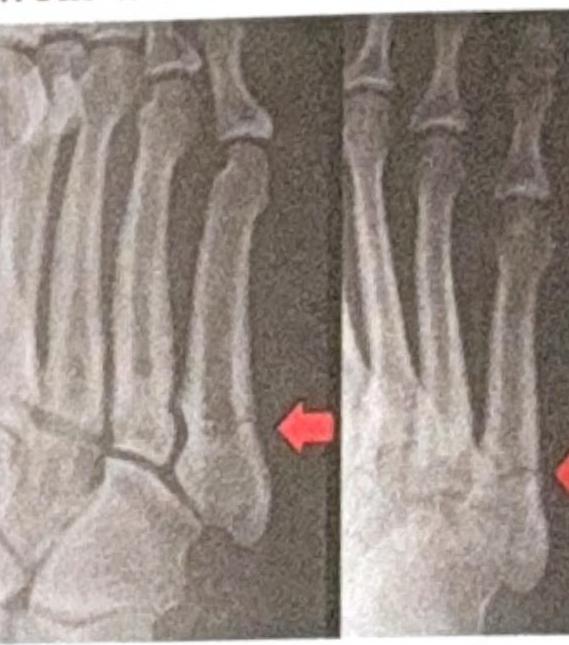

Explanation: ***Lisfranc*** - The **Lisfranc ligament** specifically connects the medial cuneiform to the base of the second metatarsal, forming a crucial part of the **tarsometatarsal joint complex**. - Its strength and integrity are vital for **midfoot stability**, and injury to this ligament can lead to significant functional impairment. *Chopart* - The **Chopart joint** (transverse tarsal joint) involves the talonavicular and calcaneocuboid articulations. - While it is a significant midfoot joint, it does not directly connect the medial cuneiform to the second metatarsal. *Deltoid* - The **deltoid ligament** is located on the medial side of the ankle, connecting the tibia to the talus, calcaneus, and navicular bones. - It primarily provides stability to the **ankle joint** and is not involved in hindfoot-to-midfoot connections. *Spring* - The **spring ligament** (plantar calcaneonavicular ligament) connects the calcaneus to the navicular bone. - It plays a crucial role in supporting the **medial longitudinal arch** of the foot, but does not connect the cuneiform to the metatarsals.